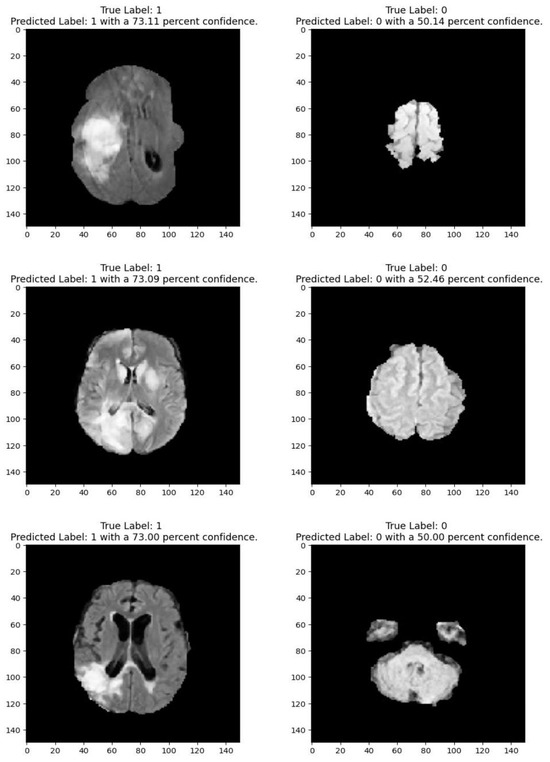

Figure 2 shows that images depicting no tumor typically reveal a serene landscape of brain tissue, characterized by uniform intensity and well-defined anatomical structures. MRI images exhibiting tumors offer a stark contrast. Within these scans, areas of heightened intensity or irregular masses emerge, signaling the presence of pathological growths. These tumors may manifest as distinct lesions, irregular masses, or regions of increased signal intensity, disrupting the otherwise orderly landscape of brain tissue. Notably, the presence of tumors often induces observable changes in adjacent structures, which may appear compressed, displaced, or distorted. By discerning these visual cues, healthcare professionals can effectively differentiate between images with no tumor and those with tumors, facilitating accurate diagnosis and informed treatment decisions for patients

Medical imaging encompasses a diverse array of variations, underscoring the significance of image detection in their interpretation. Our focus was on utilizing MRI scans for the detection of brain tumors. MRI serves as a common modality for both detecting and categorizing brain tumors. In our study, we opted to employ fine-tuned transfer learning models to aid in the identification of brain tumors due to their ability to make precise predictions regarding tumor cells. Figure 9, Figure 10, Figure 11 and Figure 12 display graphical representations of the base model combined with transfer learning operations, and Table 4 presents the corresponding findings. Figure 13, Figure 14, Figure 15 and Figure 16 illustrate the epoch-by-epoch progress of the proposed model, with Table 5 summarizing the associated results. We present a comparison in Table 6 of this study, contrasting the existing research with our proposed approach. Figure 17, Figure 18, Figure 19 and Figure 20 represent the prediction of the model in terms of tumor or non-tumor. The model, named Fine-Tuned Transfer Learning Xception, achieved the highest accuracy of 0.9611, as indicated in the table.